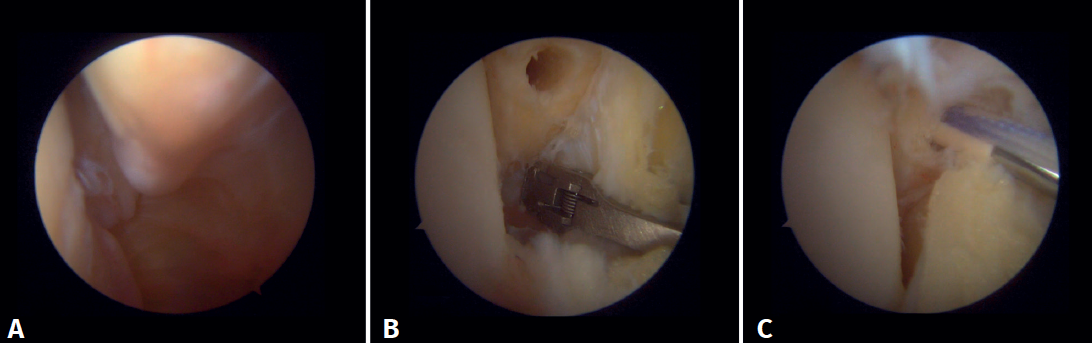

Surgical technique: arthroscopic treatment of acute syndesmosis injuries

The technique should be performed using the conventional anteromedial and anterolateral portals. The anteromedial portal is used for visualization, while the anterolateral portal serves as the working portal. Once the tibiofibular space is visualized, the inflamed synovial component is resected with an arthroscopic shaver to facilitate reduction (Figure 7A). Then, under direct vision, we restore the tibiofibular space, carefully taking into account possible malrotation of the fibula, especially in Maisonneuve type fractures. For fibular reduction we use a Verbrugge clamp, which allows us to correct the rotation. In our experience, once the space has been cleaned and if the position is correct, it is infrequent to have to use a compression clamp between the tibia and fibula.

Once the desired reduction has been achieved, we visually check the position and temporarily fix it using a Kirschner pin.

For definitive fixation, the surgical options range between rigid fixation with screws and dynamic fixation. Screws have been the standard procedure for decades, but involve complications, such as loosening or rupture. Furthermore, some surgeons advocate their removal, with the inherent risk of recurrence of instability(27). Dynamic fixation was designed to overcome some of these problems by allowing a degree of physiological movement of the syndesmosis, facilitating early weight bearing, reducing the risk of rupture, and eliminating the need to remove the implant (Figure 7B).

Figure 7. A: debridement of the tibiofibular space; B: stabilization of the syndesmosis using a suspension system.